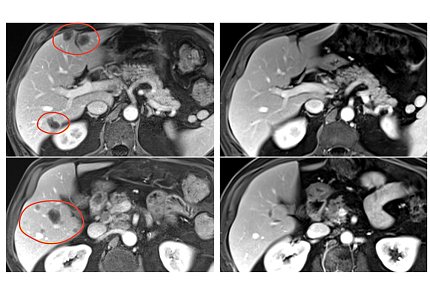

4 PET scans showing a cross-section of a person's body. The 2 left images show lesions on the liver, circled in red. The lesions are much smaller

Ten months after treatment with selected TIL therapy and pembrolizumab, a patient with rectal cancer had substantial shrinkage of multiple liver metastases (left scans, circled in red).